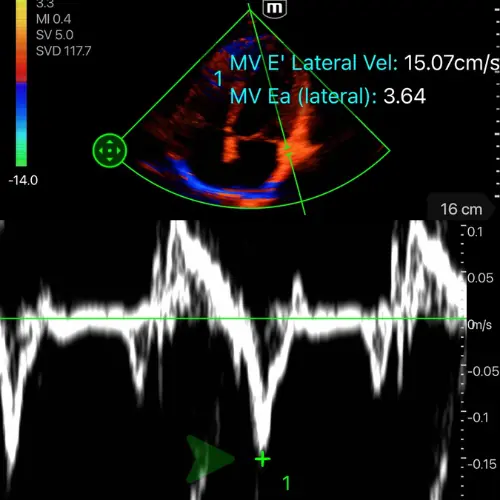

Fonction diastolique et précharge

Le remplissage, ou l’art de savoir quand s’arrêter